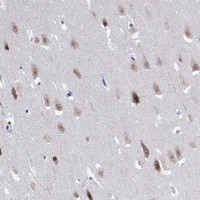

Immunohistochemical staining of human hippocampus shows nuclear and cytoplasmic positivity in neurons.